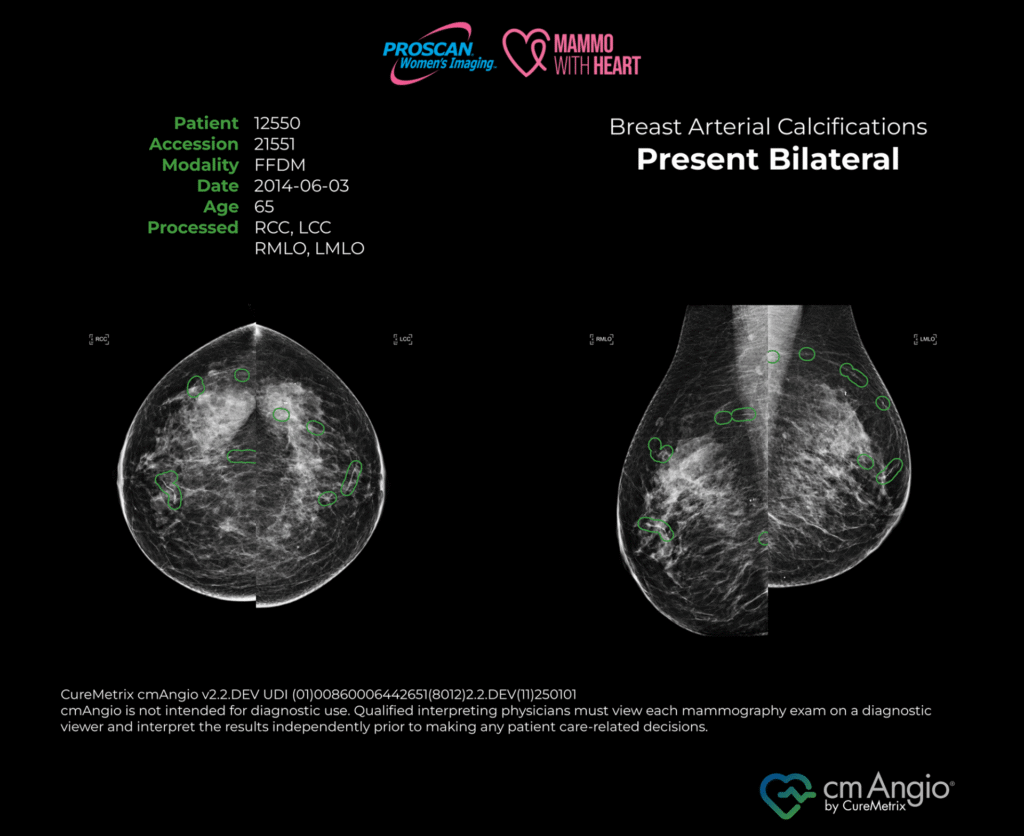

Mammo with Heart is an FDA-cleared, artificial intelligence (AI) based software intended to detect the presence or absence of breast arterial calcifications (BAC), a calcium build-up in the arteries of the breast and a potential indicator of increased cardiovascular disease risk..

The cmAngio software reads your mammogram images to determine the presence or absence and location of Breast Arterial Calcification. An expert radiologist will review your results to confirm the findings.

Mammo with Heart utilizes cmAngio®, an FDA-cleared artificial intelligence (AI) detection software, to determine the presence or absence of breast arterial calcification (BAC) as an incidental finding in standard-view screening mammograms. The cmAngio® software is not FDA-cleared for use with screening mammograms that require displacement or alternative views; therefore, Mammo with Heart is not available to patients who need alternative views for their screening. The detection of BAC indicates calcium buildup within the breast arterial wall. While BAC has been associated with an increased risk of coronary heart and cardiovascular disease, its presence or absence does not constitute a diagnosis and should not be used alone to determine cardiovascular risk. Results from Mammo with Heart may support further clinical evaluation or patient management at the discretion of a primary care physician, cardiologist, or other specialist. If BAC is detected, please consult your healthcare provider for additional information, assessment, or treatment options.